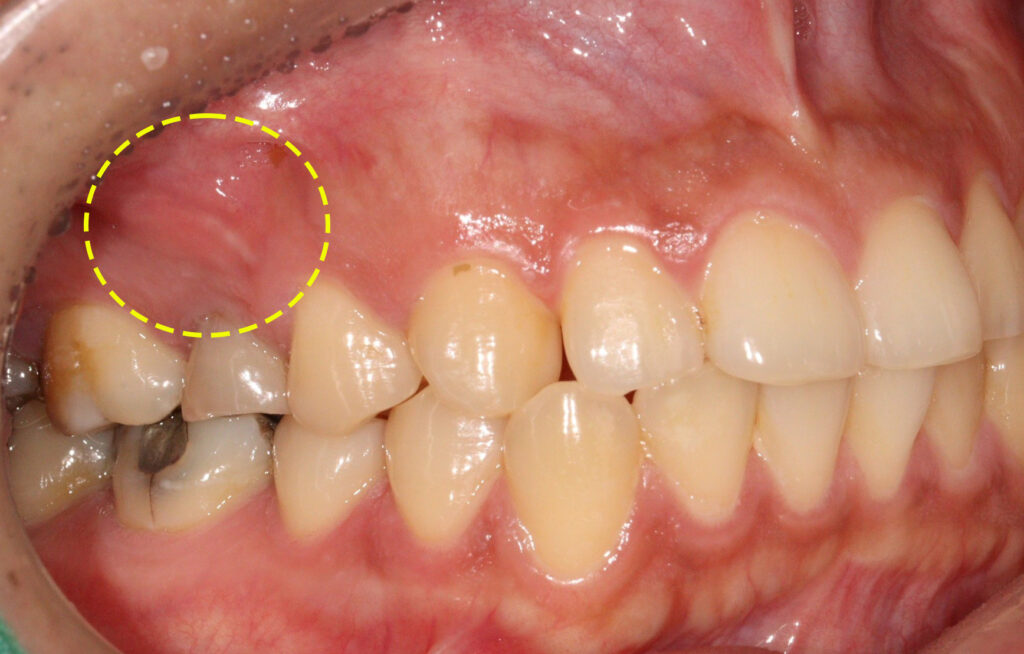

환자분께서는 신경치료 후 크라운을

진행하지 않았던 오른쪽 위 작은 어금니

뿌리의 큰 낭종이 생겨 있는 상태였는데요.

위턱뼈의 3개 치아가 넘는 크기의

낭종으로 제거가 필요한 상황임을

설명드리고 치료 계획을 수립하였습니다.

이후 치근단 절제술을 시행하였는데요.

사이즈가 너무 크다 보니 보통은 잘 하지 않지만

뼈이식을 함께 진행하였습니다.

치근단절제술은 치아 뿌리 끝에 생긴

염증이나 낭종을 외과적으로 제거하는 수술로

보통 신경치료를 받은 후에도 뿌리 끝 주변 조직에

세균이 침투하거나 치근관의 해부학적 구조가 복잡해

약물이 끝까지 도달하지 못할 때 시행됩니다.

재신경치료로 해결되지 않는 경우에 한해

치아의 뿌리 끝을 절제해 염증 부위를

직접 정리함으로써 통증과 감염을 차단하는 것이 목적입니다.